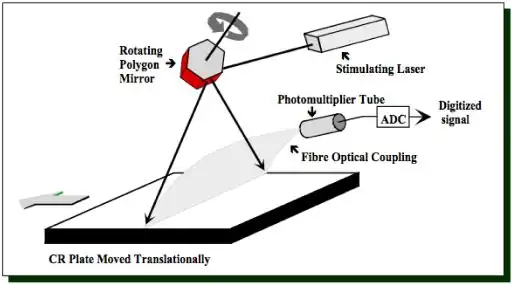

- The readout stage is shown in more detail in our next figure:

- The figure illustrates one mechanism used to scan the imaging plate where a narrow laser beam strikes a rotating mirror causing it to scan a single line across the plate. The plate is then moved so that the scanning laser beam can read the next line of the latent image information.

- The latent image is formed through radiation absorption processes in the photostimulable phosphor where electrons are knocked into higher energy states where they remain until they're later stimulated to return to their ground states using the red laser beam – a process similar to thermoluminescence where light is used instead of heat. The electrons emit blue light – called a photostimulable luminescence (PSL) – as they return to their ground states with the amount of light being proprotional to the radiation exposure.

- The emitted light is guided by a light guide, as shown in the figure above, so that its intensity can be measured using a photomultiplier tube (PMT). The output of the PMT is digitized using an analogue-to-digital converter (ADC) before computer processing is applied.